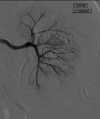

Arterioureteral fistula (AUF) is a direct communication between the ureter and an artery and is a rare cause of catastrophic, life-threatening haematuria. Fistulation may occur between the ureter and the abdominal aorta, common iliac, external and internal iliac, and inferior mesenteric arteries, and is typically observed in patients with a prior history of pelvic radiotherapy, oncological pelvic surgeries, aortoiliac vascular procedures, and pelvic exenteration. There is also an increased frequency of cases amongst patients who have undergone urological diversion surgeries and in those with chronic indwelling ureteric stents requiring repeated exchange. As AUF is so rarely encountered in clinical practice, the urologist may fail to appreciate its presence until late in the patient's presentation; such diagnostic delay is associated with high mortality and thus rapid clinical suspicion and investigative action are necessary. There are sporadic cases of this rare entity mentioned in literature. In this report, we present two cases as well as a review of the literature. A 73-year-old female presented with repeated episodic haematuria for a week in whom the cause of symptoms remained persistently elusive despite repeated imaging and operative approaches. An eventual diagnosis of a secondary right internal iliac-ureteral fistula was ascertained on a subsequent digital subtraction angiography of the renal tract. The fistula was embolised using an endovascular approach. The patient remained stable post emobilisation and was successfully discharged shortly after the procedure. In the second case, a 51-year-old female, presented with hematuria from her ileal conduit for a few days. Initially, the cause of symptoms was thought to be due to ureteric stents. During a change in her stents, brisk bleeding led to further investigation including an iliac angiogram confirming bleeding from the left common iliac artery. She had a covered common iliac artery stent, which successfully controlled her bleeding This report emphasizes the diagnostic difficulty of AUF, outlines the management principles of this rare disease, and aims to increase awareness of this rare yet potentially lethal phenomenon among practitioners of urology and interventional radiology.